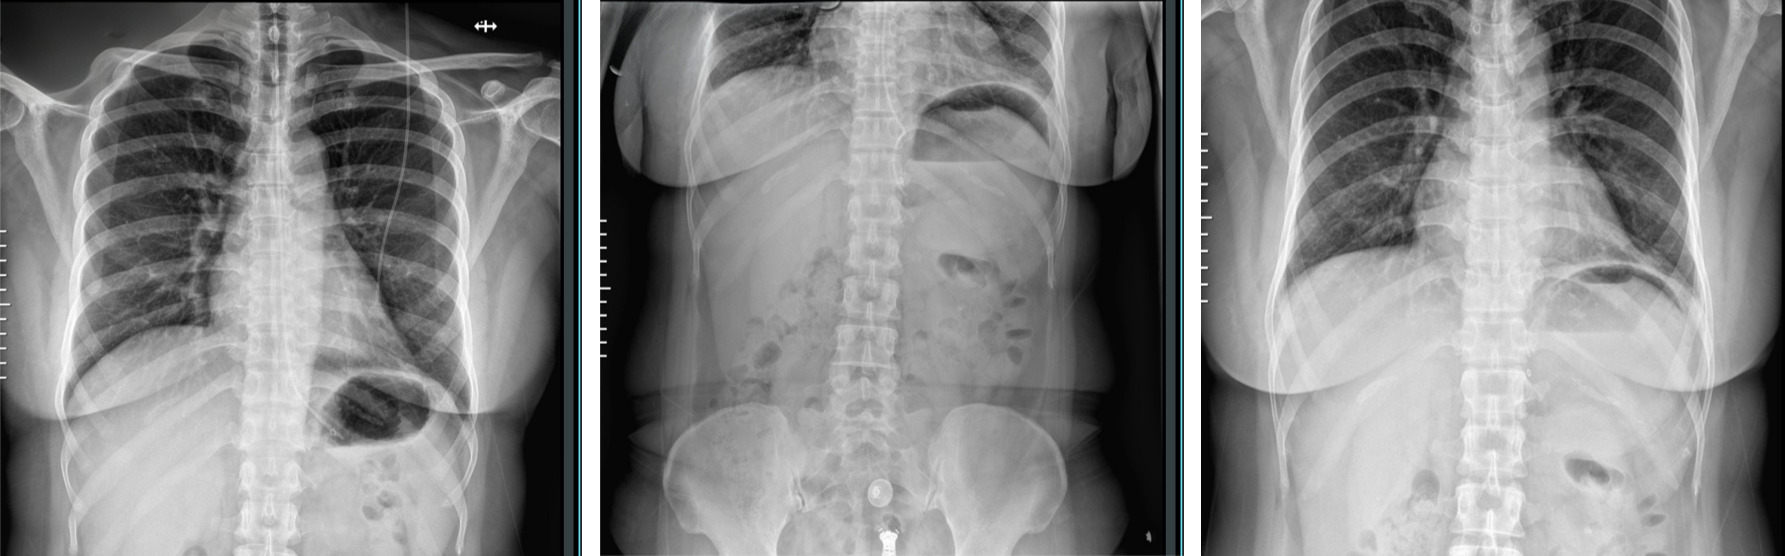

醫(yī)生通過X光確認球囊位置。

圖1為充注前影像,可見膠囊已順利到達胃部;圖2、3為充注后影像,球囊充分膨脹,位置良好。